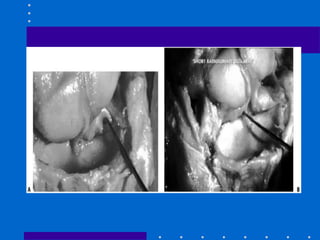

Fixação Externa

+ Redução aberta e fixação

interna

• Cominuição dorsal e volar de alta energia,

fragmentos não permitindo fixação interna

somente

• Varias coortes com sucesso

• Evita abordagem dupla dorsal e volar

• Figura 26-22

Fratura Articular Palmar

Cisalhamento

• Redução anatômica articular e compressão

através da fratura

• Placa de apoio palmar é ideal

• Cuidar: placa deve apoiar fossa lunar e se

fratura dorso radial a placa submoldada

pode deslocar dorsalmente o fragmento

distal

• Fig 26-29

A,B Tração não reduziu córtex palmar C,D Placa

volar com cominuição estilóide radial residual E,F

placa de coluna radial utilizada( pode ser Fio K)